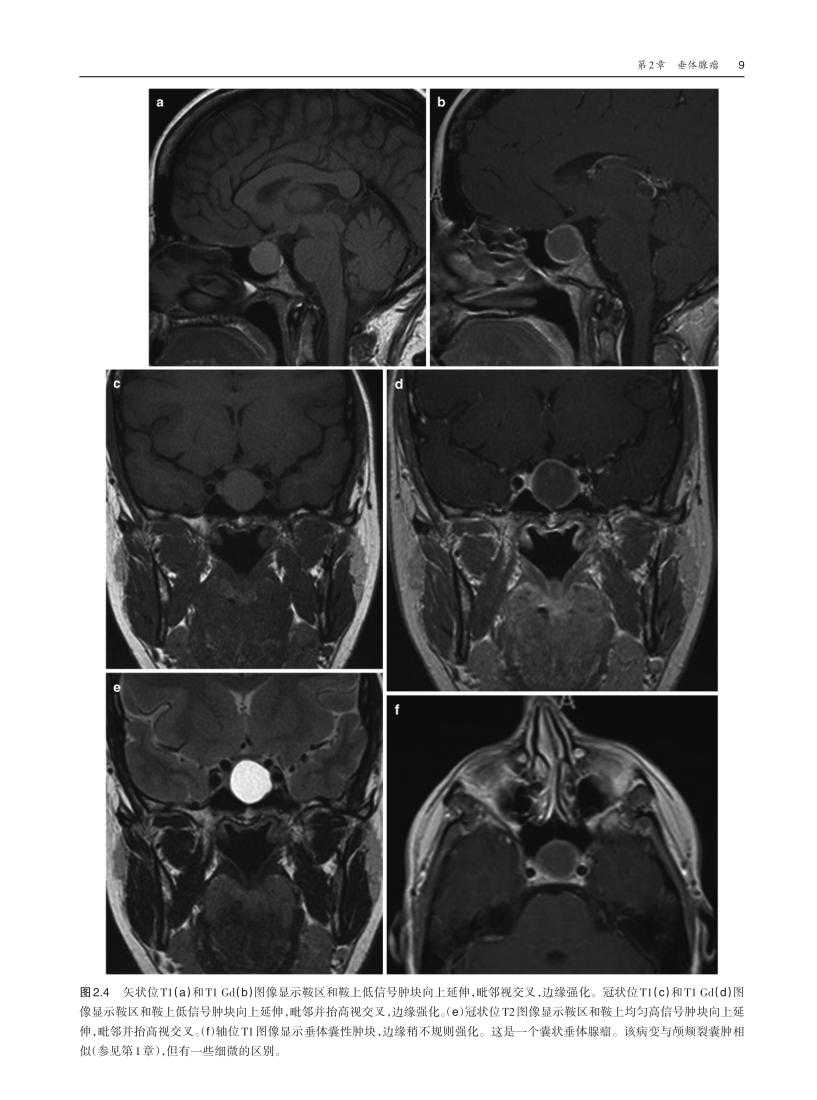

l 配以大量丰富的影像图片,以及部分解剖图片,可以帮助读者更好地掌握颅底解剖结构及颅底疾病的影像特点,便于读者学习。